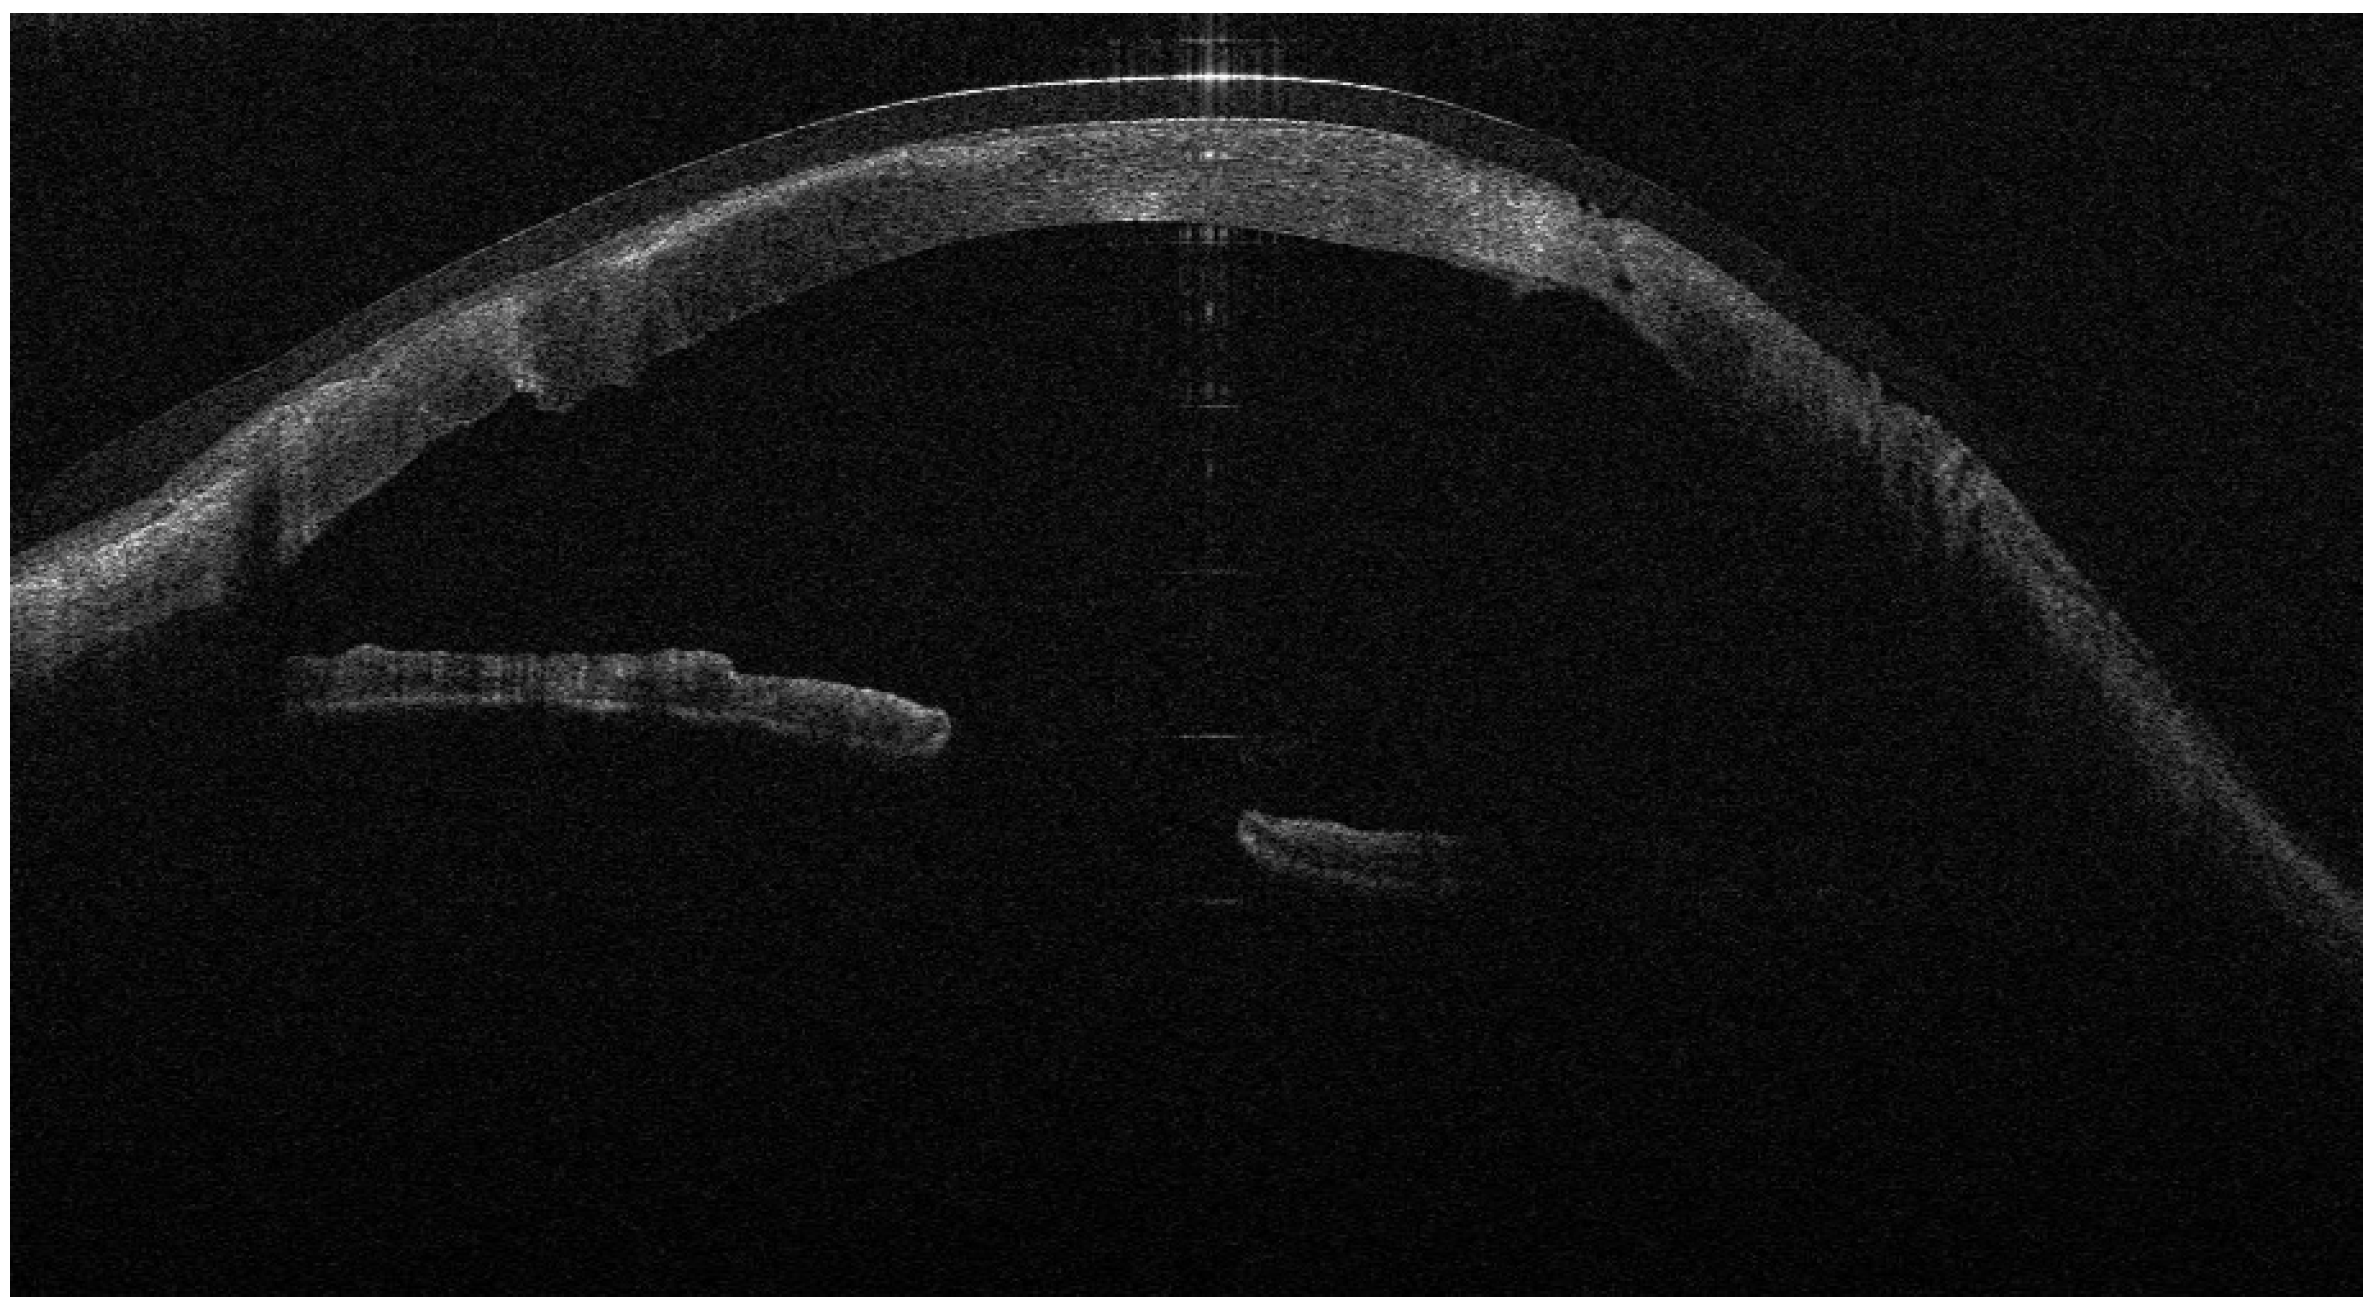

Figure 4. AS-OCT showing the donor tissue circumferentially surrounded by folded AM, creating a continuous ‘envelope’ at the graft–host junction.

Recurrent ulceration over the graft required a second patch procedure in March 2024. Subsequently, in April 2024, a full-thickness 8.25 mm PKP was performed. During penetrating keratoplasty, the donor lenticule (8.25 mm) was similarly wrapped using cryopreserved AM. The membrane was folded in a U-shaped configuration around the donor cornea, extending beyond the graft margins to cover the graft–host interface circumferentially. The same orientation was maintained (stromal side inward, epithelial side outward). The graft was then sutured to the recipient cornea with interrupted 10-0 nylon sutures, anchoring both the donor tissue and the AM envelope simultaneously. (Figure 3, Figure 4 and Figure 5).